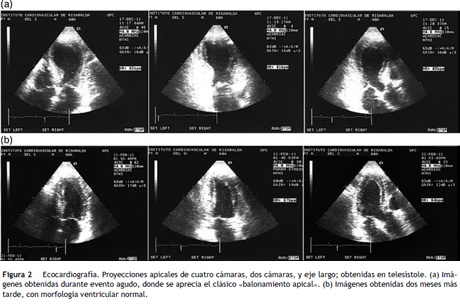

Descripción del caso

Mujer de 60 años de edad, con antecedentes de: hipertensión arterial controlada con 50 mg/día de losartan y episodios esporádicos de migraña clásica desde la juventud. Consulta al servicio de urgencias por un episodio de migraña que fue manejado con 100 mg de tramadol intramuscular, con mejoría parcial. Fue dada de alta, regresando dos horas más tarde por incremento en la intensidad de la migraña e inicio de dolor opresivo medioesternal de intensidad moderada, en los últimos veinte minutos. Al reingreso tenía: la presión arterial 150/90 mmHg, el pulso 95/min, la frecuencia respiratoria 18/min, la saturación periférica de oxígeno 98% respirando aire ambiente; sin hallazgos anormales al examen físico. El electrocardiograma (fig. 1), mostró elevación del segmento ST en V2 y V3 y la ecocardiografía (fig. 2a), acinesia de los segmentos apicales y medios de las diferentes paredes del ventrículo izquierdo con «balonamiento apical» y una fracción de eyección del 27% por el método de Simpson modificado; hallazgos que conducen a plantear un diagnóstico presuntivo de la miocardiopatía de takotsubo. Treinta minutos posteriores al ingreso, se le realizó un cateterismo cardiaco (fig. 3a), encontrándose una arteria coronaria única que se originaba en el ostium coronario derecho, sin encontrarse lesiones angiográficas o vasoespasmo. La arteria coronaria única derecha era hiperdominante, bordeaba el surco auriculoventricular posterior. El árbol coronario izquierdo estaba poco desarrollado con ausencia del tronco coronario común izquierdo. La coronaria descendente anterior y la circunfleja, tenían orígenes independientes en la coronaria derecha proximal. La arteria descendente anterior, seguía un trayecto anterior hacia la izquierda sobre el tracto de salida del ventrículo derecho alcanzando el surco interventricular anterior. La arteria circunfleja, de mayor longitud que la arteria descendente anterior, seguía un trayecto posterior hacia la izquierda, entre los grandes vasos y la aurícula izquierda. Durante la realización de la coronariografía, el dolor torácico desapareció espontáneamente sin reaparecer posteriormente. La paciente fue manejada con enoxaparina a dosis de anticoagulación, ácido acetil salicílico, carvedilol, enalapril y atorvastatina. La troponina T obtenida a las 12 horas del ingreso fue de 0.566 ng/ml (vn 0-0.014), con control de 0.377 ng/ml 24 horas después del ingreso, con la creatinfosfoquinasa total de 246 U/L (vn 0-190) y MB de 39.8 (vn 0-24), TSH 1.41 uUL (vn 0.27-4.2), el sodio 145 mmol/lt (vn 135-149), el potasio 4.1 mmol/lt (vn 3.5-5.1) y la creatinina sérica de 0.66 mg/lt. Diez días más tarde, la paciente fue dada de alta con el tratamiento que venía recibiendo y la anticoagulación con la warfarina. Como estudios adicionales, se realizaron: una tomografía computarizada simple del cráneo, que fue normal y una angiotomografía coronaria multicorte (fig. 3b) que confirmó los hallazgos de la coronariografía, excluyendo el trayecto interarterial de algún brazo coronario mayor. El electrocardiograma (fig. 1) y la ecocardiografía de control (fig. 2b) realizados dos meses más tarde, fueron normales. Un estudio de perfusión miocárdica de estrés con ejercicio realizado a los 30 días, fue normal. Teniendo en cuenta la edad, la ausencia de síntomas previos atribuibles a la isquemia miocárdica, la perfusión miocárdica normal y la ausencia de lesiones coronarias o el trayecto interarterial de un brazo mayor; no se consideró algún procedimiento de la revascularización. Transcurridos 12 meses posteriores al evento agudo, la paciente ha permanecido asintomática con manejo farmacológico.

Los pacientes con la miocardiopatía de takotsubo, presentan elevación de los niveles de la creatinfosfoquinasa en el 74% de los casos y de la troponina en el 86%, con valores bajos que no se correlacionan con lo esperado de acuerdo a la extensión del daño miocárdico evaluado por el electrocardiograma o las imágenes1,5. En pacientes con infarto agudo del miocardio, se ha encontrado que un valor de la troponina T superior a 2.8 ng/ml, en mediciones realizadas entre 12 a 48 horas posteriores al inicio del dolor, se correlacionan con la fracción de eyección del ventrículo izquierdo menor del 40%6. En el caso presentado, la disfunción sistólica severa del ventrículo izquierdo no se correlacionó con los valores de la troponina encontrados (0.566 ng/ml), apoyando el diagnóstico de la miocardiopatía de takotsubo. Los pacientes con la miocardiopatía de takotsubo, presentan una fracción de eyección del ventrículo izquierdo del 20 al 49%, que se normaliza en días a semanas, con promedio de 18 días7. La ecocardiografía en este caso, mostró una fracción de la eyección del 27%, con recuperación completa en el control realizado dos meses más tarde.